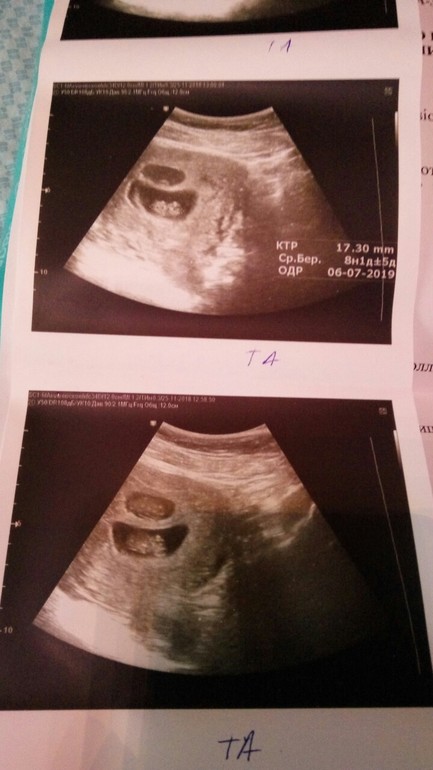

Продолжение 8 недели: УЗИ: ПЯ одного все еще меньше второго...один 15 мм второй 13 мм...растем